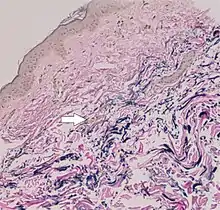

- Diagnostic histopathological changes in lesional skin: Calcified elastic fibers in the mid and lower dermis, confirmed by positive calcium stain

| Pseudoxanthoma elasticum | LM: Mid-dermal calcification and fragmentation of elastic fibers EM: Mineralization in elastic fiber core |

In PXE, there is mineralization (accumulation of calcium and other minerals) and fragmentation of the elastin-containing fibers in connective tissue, but primarily in the midlaminar layer of the dermis, Bruch's membrane and the midsized arteries.[26] Recent studies have confirmed that PXE is a metabolic disease, and that its features arise because metabolites of vitamin K cannot reach peripheral tissues.[27] Low levels of PPi cause mineralization in peripheral tissues.[19]